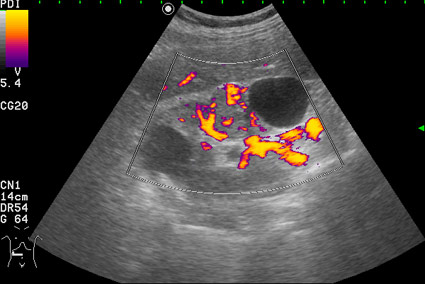

Сканирование в режиме энергетического доплера.

Вас не смущает наличие внутреннего кровотока в одной из "кист"?

Но Вы правы в том, что могут быть трудности в дифференциальном диагнозе между AML и RCC малых размеров (в 20-30 % случаев могут быть эхогенными). Однако при УЗИ для RCC характерен гипоэхогенный ободок, внутриопухолевые включения, низкорезистивный внутриопухолевый кровоток.